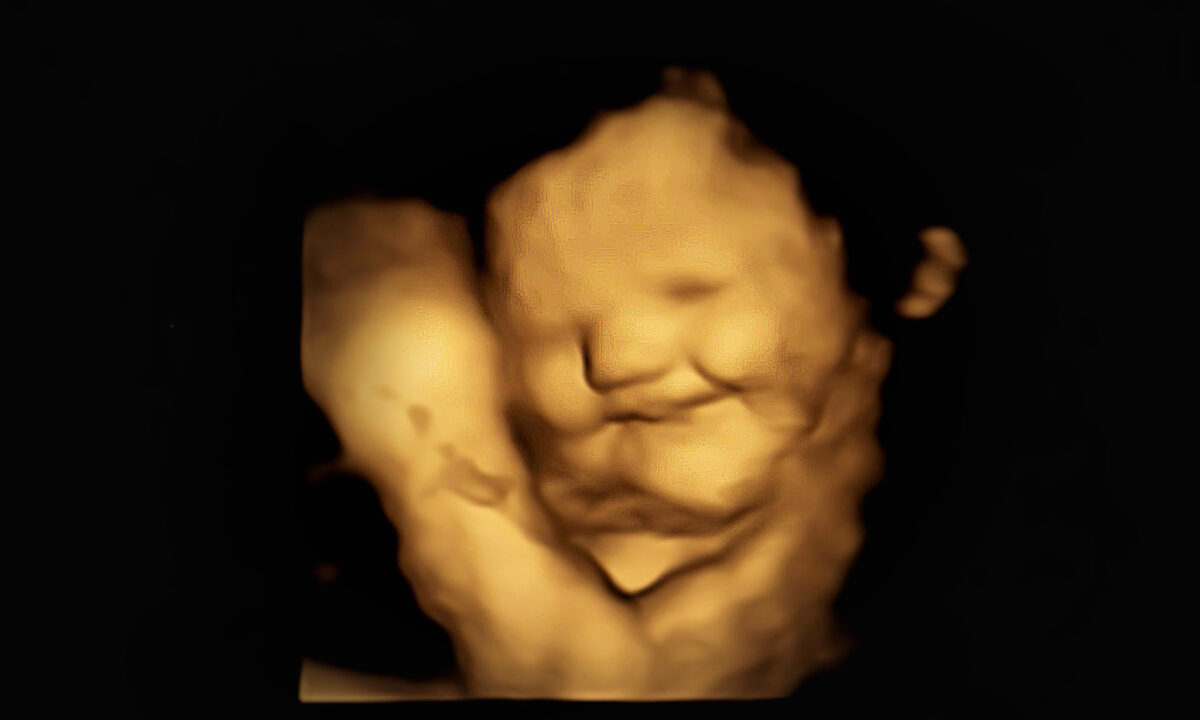

Các nhà nghiên cứu đã sử dụng phương pháp siêu âm 4D mã hóa và xác định được những chuyển động phức tạp trên khuôn mặt của em bé khi mẹ ăn cà rốt (có vị ngọt) và cải xoăn (có vị đắng) và xác nhận giả thuyết của họ là đúng: những em bé có mẹ ăn cà rốt có nhiều nụ cười hơn, những bé có mẹ ăn cải xoăn có nhiều biểu hiện khóc trên khuôn mặt hơn. Các chuyển động trên khuôn mặt của bé được đo theo từng khung hình, tiết lộ phản ứng khi mẹ bé ăn các loại thức ăn khác nhau.

Các nhà nghiên cứu của Khoa Tâm lý học trường Đại học Durham cùng với các nhà khoa học của trường Đại học University of Bourgogne và Đại học Aston đã làm thử nghiệm với những phụ nữ mang thai và thai nhi được từ 32 đến 36 tuần ở khu vực đông bắc nước Anh. Mỗi người được cho uống một liều loại viên nang gồm cà rốt, cải xoăn, hoặc không có hương vị.

Các nhà nghiên cứu phát hiện ra rằng những thai nhi tiếp xúc với hương vị cà rốt có biểu hiện “kéo khóe môi” và “cử chỉ mặt cười” thường xuyên hơn so với những thai nhi tiếp xúc với hương vị cải xoăn – có biểu hiện “hạ môi dưới” và “cử chỉ mặt khóc.” Hương vị cà rốt tổng hợp được người lớn mô tả là “ngọt ngào” vì hàm lượng đường của nó và đôi khi cà rốt cũng có hương vị trái cây hoặc hương gỗ. Cải xoăn cũng được chọn để thử nghiệm vì có nhiều vị đắng hơn các loại rau xanh khác như rau bina, bông cải xanh hoặc măng tây.

Hơn nữa, thí nghiệm cũng xác nhận một giả thuyết khác rằng độ phức tạp của các biểu hiện trên khuôn mặt của thai nhi tăng lên khi tuổi thai tăng từ 32 đến 36 tuần, đặc biệt là khi tiếp xúc với hương vị cải xoăn chứ không phải cà rốt.